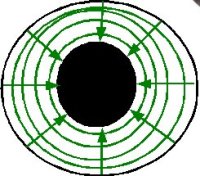

El iris tiene unas fibras radiales, dilatadoras, midriásicas. |

También tiene unas fibras concéntricas, constrictoras, mióticas. |

A nivel fisiológico, podemos regular el tamaño de la pupila aplicando una luz intensa en ella (produciremos miosis) o dejando al paciente en la oscuridad (produciéndose midriasis). Y esto se debe al reflejo pupilar: que evalúa el par II (óptico) como sensible y al par III (oculomotor) como via visceroeferente. (click para agrandar la imagen). |